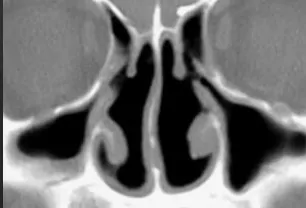

В Москве мужчина, работающий менеджером в сотовой компании, совершил попытку самоубийства после того, как увидел рентгеновский снимок человека, страдающего синдромом «пустого носа». Он подвергся операции на носовой перегородке в 2022 году и неправильно решил, что у него схожая проблема.